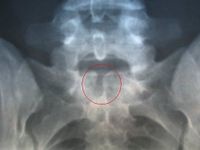

ما هى أنواع الصلب المشقوق؟ هناك 3 أنواع من الصلب المشقوق تشمل: الصلب المشقوق الخفي: و لا يمكن الكشف عنه بدون اجراء أشعة على الظهر، فالصلب المشقوق الخفي لا يمكن الكشف عنه عن طريق الفحص السريري لطفلك. الصلب المشقوق الكيسي: و هو أكثر الأنواع خطورة، و يكون عبارة عن كيس يحتوي على جزء من الحبل الشوكي، و كذلك الأعصاب المحيطة بالحبل الشوكي، من الممكن أن يؤدي لحدوث شلل تام، و في بعض الأحيان قد يصل الأمر للوفاة إذا لم يتم علاجه بطريقة صحيحة. أسباب الصلب المشقوق ( السنسنة المشقوقة ) العوامل الوراثية و العوامل البيئية، مثل التغذية و التعرض للمواد الضارة ربما تسهم في حدوث الصلب المشقوق. إنجاب طفل مصاب بالصلب المشقوق يزيد من فرصة إصابة الطفل الثاني 8 مرات و مع ذلك فحوالي 95 من حالات الإصابة بالصلب المشقوق لا يوجد بها تاريخ عائلي سابق. قد أشارت الأبحاث إلى أن نقص حمض الفوليك قد يؤدي لحدوث الصلب المشقوق لدى الأطفال، لذا يتم تناول أقراص حمض الفوليك عند التفكير في الحمل لحماية طفلك.

- مكان الإصابة وحجمها تكون الإصابة في أي منطقة في العمود الفقري، ويختلف حجم الإصابة وشكلها، فقد تكون صغيرة وفي فقرة واحدة، أو كبيرة وفي عدة فقرات، وبحسب مكان الإصابة ونوعها تختلف التأثيرات أو حجم الإعاقة.

- الصلب المشقوق المستتر Spina bifida occulta - التورم السحائي Meningocele - التورم النخاع السحائي Myelomeningocele أنه لوحظ أن هناك نسبة تصل لخمسة في المائة من الناس يوجد لديهم عدم انغلاق لإحدى الفقرات، ومن دون وجود أي أعراض مرضية.

Spina bifida occulta